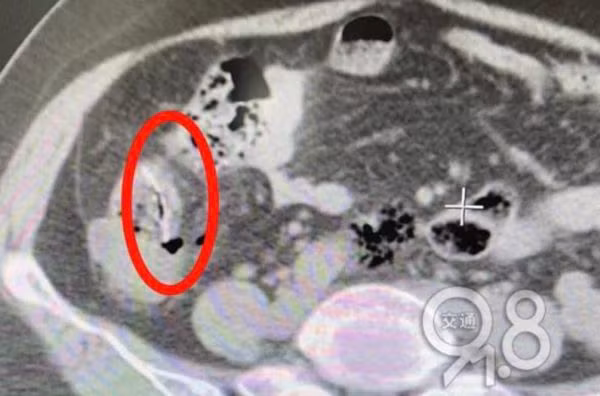

Sau khi khám, bác sĩ phát hiện bạch cầu của người phụ nữ tăng quá mức nghiêm trọng, đây là dấu hiệu cảnh báo bệnh viêm phúc mạc, trong ruột non có những mảnh dị vật, nghi là xương cá mà cô đã nuốt phải vài ngày trước.

Bác sĩ cũng phát hiện trong khoang bụng người phụ nữ có một lượng lớn dịch có mủ, một chiếc gai cá khổng lồ ở hồi tràng đã đâm vào ruột non, lộ ra đầu ruột.